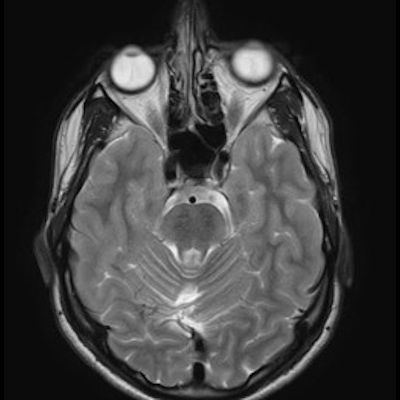

11 ay, Nöbet

Charlevoix-Saguenay Otozomal Resesif Spastik Ataksisi (ARSACS)

ARSACS (Charlevoix-Saguenay otozomal resesif spastik ataksisi) Sendromu

ARSACS

Autosomal recessive spastic ataxia of Charlevoix-Saguenay

Serebellar folya sinapsisi